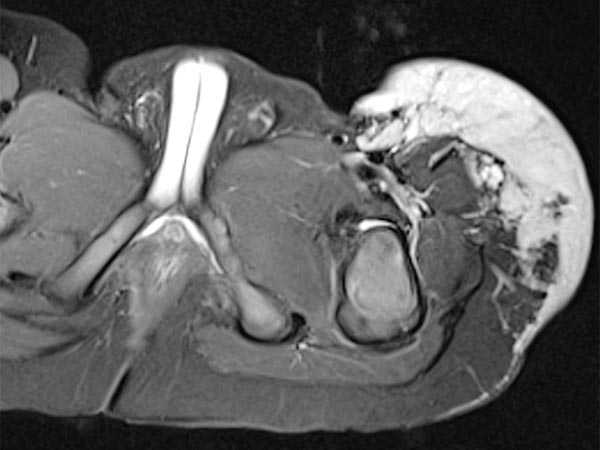

Auch in der axialen Schichtführung der MRT (T2-gewichtet, fettgesättigt) ist die Infiltration der Muskulatur durch die Raumforderung gut dargestellt. Auch Hämangiome können als vaskuläre Tumoren eine solche Infiltration aufweisen, ohne dass sie maligne sein müssen.

Die axiale T2-Wichtung ohne Fettsättigung zeigt den Tumor homogen nur gering hyperintens. Er ist zwar hyperintenser als Muskulatur, aber insgesamt deutlich weniger hyperintens als das umgebende subkutane Fettgewebe.